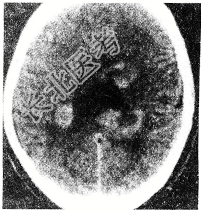

- 单项选择题男性患者,38岁。3个月前行肺癌切除术, 近3周来出现头痛、呕吐及阵发性意识错乱并有2次癫痫发作。检查:神情淡漠, 视盘鼻侧边缘模糊,胸部除前次术后一般改变外, 无其他重要发现,血沉50mm/h。头颅超声波检查: 中线波无偏移。脑电图:双侧弥漫性异常, 头部CT扫描显示双侧大脑半球皮质及皮质下区多个小圆形低密度灶(如图所示)。处理应为